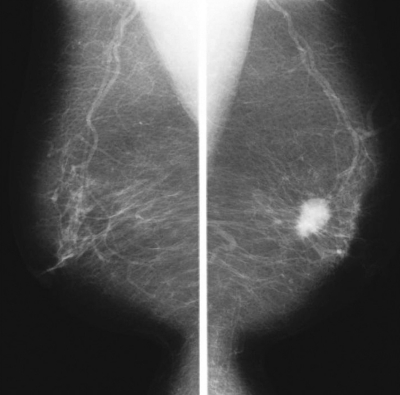

64歳の女性。乳がん検診のマンモグラフィで異常を指摘され来院した。左乳房に長径約2cmの腫瘤を触知する。腫瘤は境界不明瞭で硬く圧痛を認めない。乳頭からの分泌物を認めない。マンモグラムを示す。

次に行うべき検査はどれか。2つ選べ。